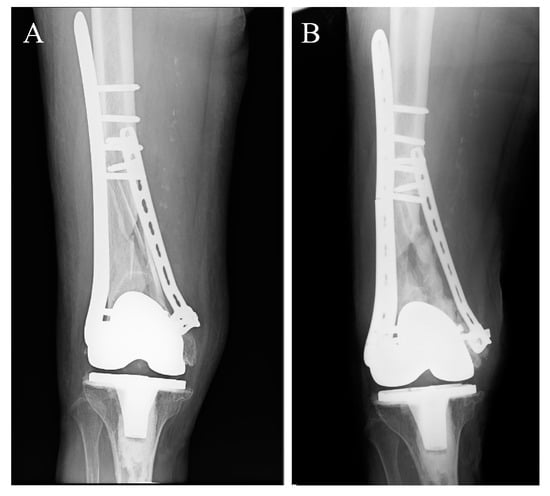

- Ito, K.; Mori, Y.; Kamimura, M.; Koguchi, M.; Kurishima, H.; Koyama, T.; Mori, N.; Masahashi, N.; Hanada, S.; Itoi, E.; et al. beta-type TiNbSn Alloy Plates With Low Young Modulus Accelerates Osteosynthesis in Rabbit Tibiae. Clin. Orthop. Relat. Res. 2022, 480, 1817–1832. [Google Scholar] [CrossRef] [PubMed]

- Koguchi, M.; Mori, Y.; Kamimura, M.; Ito, K.; Tanaka, H.; Kurishima, H.; Koyama, T.; Mori, N.; Masahashi, N.; Aizawa, T. Low Young’s Modulus TiNbSn Alloy Locking Plates Accelerate Osteosynthesis in Rabbit Tibiae. Tohoku J. Exp. Med. 2023, 261, 199–209. [Google Scholar] [CrossRef] [PubMed]